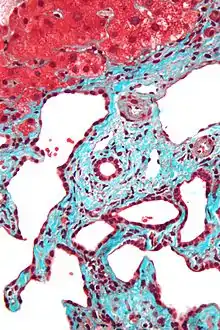

Micrograph of a bile duct hamartoma. Trichrome stain. Intermediate magnification

Micrograph of a bile duct hamartoma. Trichrome stain, high magnification

Low magnification micrograph of a bile duct hamartoma. Trichrome stain.